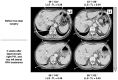

Methods: Fifty computed tomography (CT) scans obtained in subjects with normal liver were studied. Four CT scan levels were preselected: level 1 passed by the upper part of the hepatic veins; level 2 passed by the left portal vein branch division; level 3 passed by the right portal vein branch division, and level 4 passed by the gallbladder bed. Left and right tangent lines passing the liver edges were drawn and joined to the centre of the vertebra defining the TL angle. Two lines through, respectively, the plane of the middle hepatic vein and the left portal branches determined the angles of the RL, LL and LLS. Volumetric and angulometric data obtained on levels 2 and 3 in 50 different subjects were compared.

Results: Level 2 CT scans represented the most accurate way of obtaining angulometric measurements. The mean ± standard deviation (SD) angles of the TL and LL were 134 ± 12 ° and 55 ± 12 °, respectively. The mean ± SD percentages of the TL represented by the LL in angulometry and volumetry were 38 ± 7% and 36 ± 6%, respectively (non-significant difference). The mean ± SD percentages of the TL represented by the LLS in angulometry and volumetry were 25 ± 4% and 20 ± 3%, respectively (P < 0.05). The mean ± SD overestimation of the percentage of the TL represented by the LLS in angulometry was 2.7 ± 7.0%.

Conclusions: Angulometry is a simple and accurate technique that can be used to estimate the ratio of the FLR to TL volume on one or two CT (or magnetic resonance imaging) slices. It can be helpful for clinicians, especially before right or extended right hepatectomy and after right portal vein occlusion techniques.